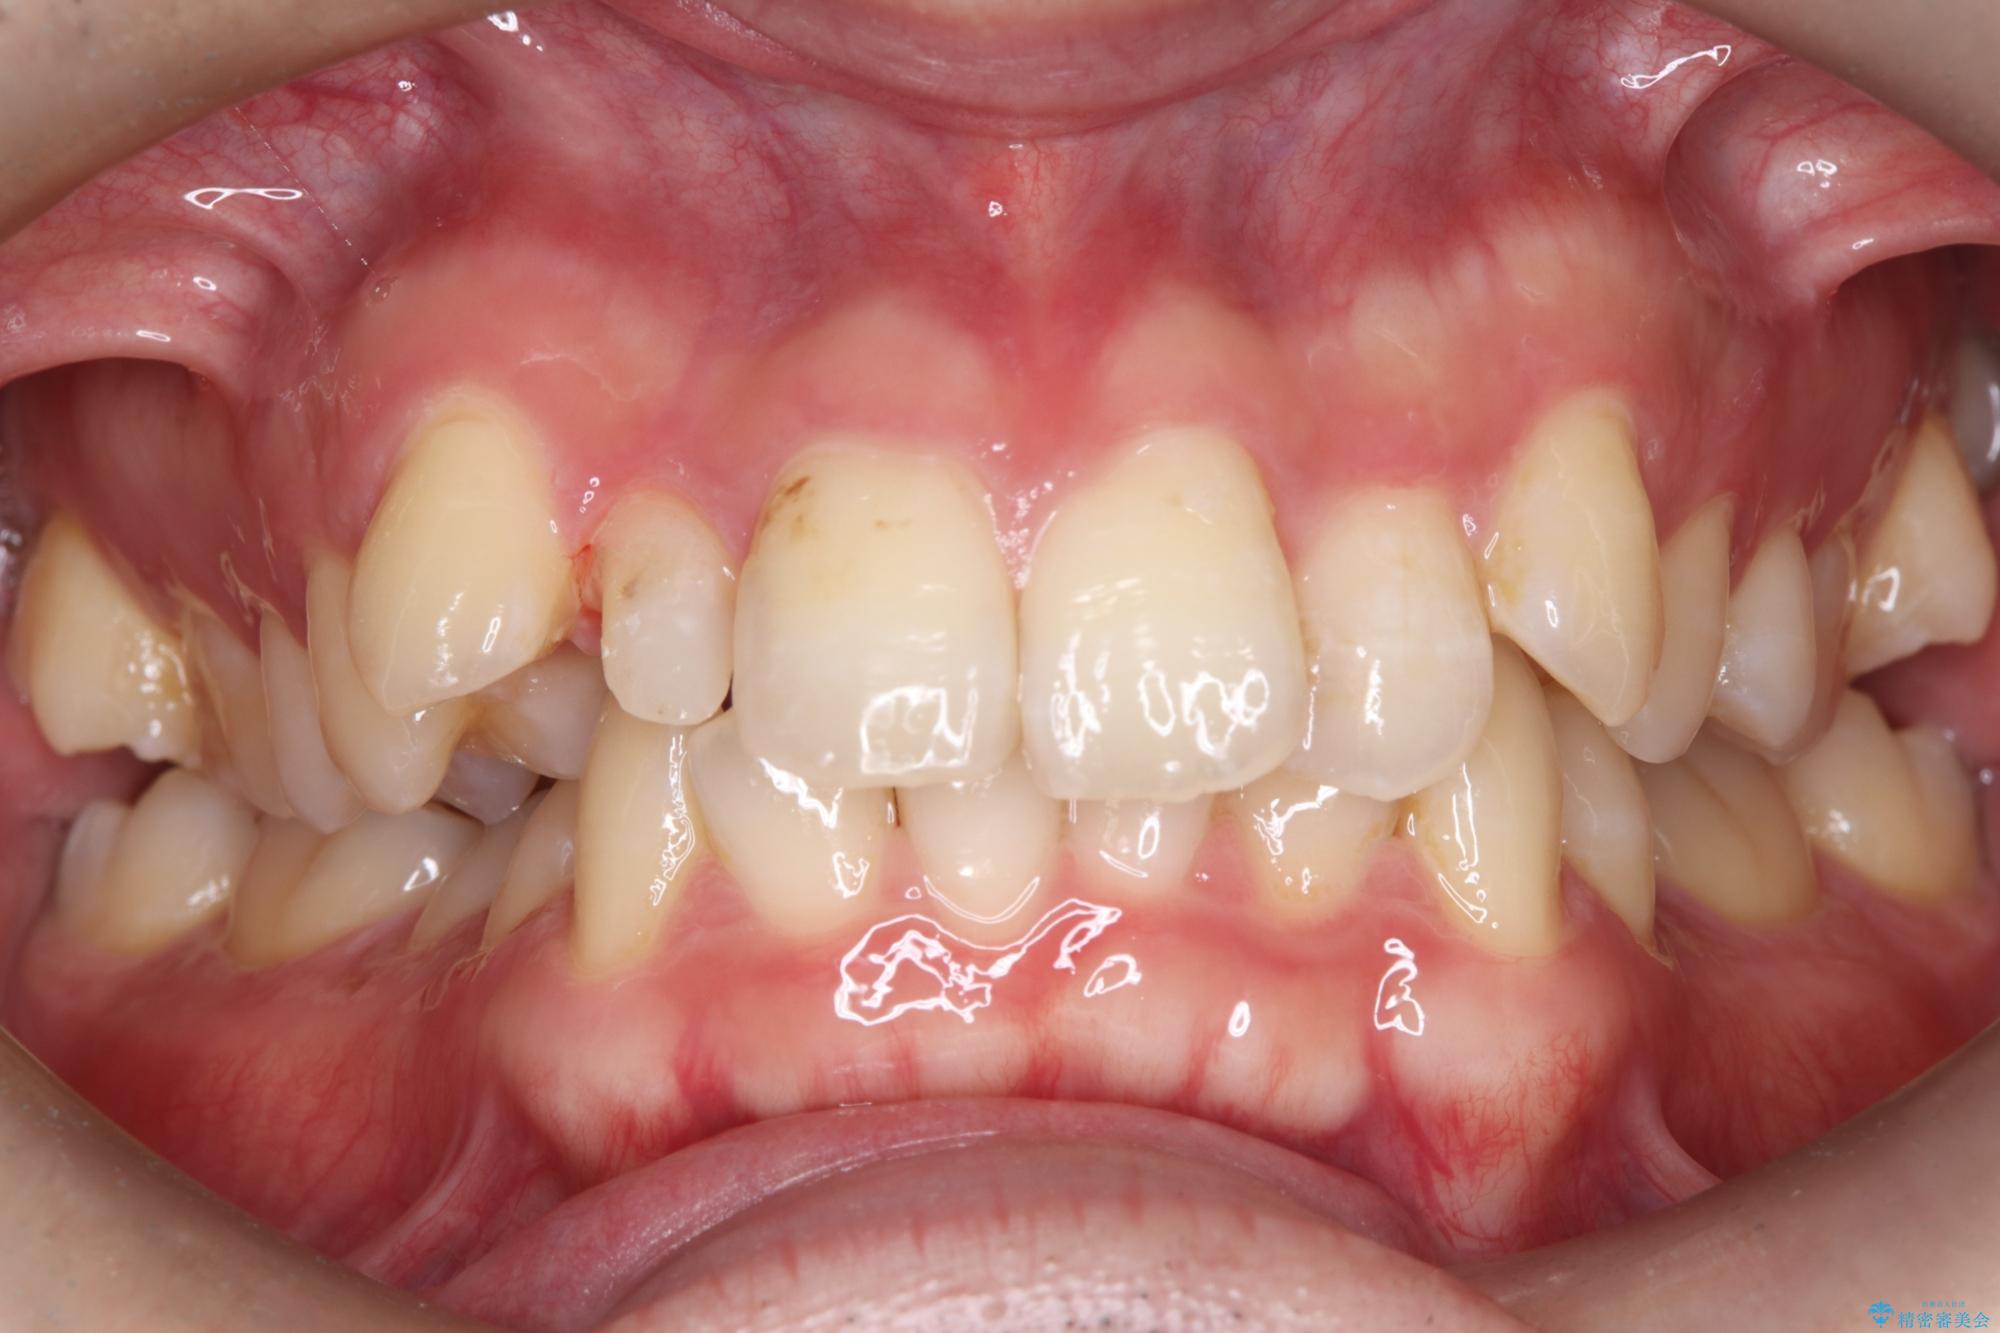

- 主訴:右上の前歯が何しなくても痛い

右上2番の歯に自発痛を認め、症状や歯髄診・レントゲン像から不可逆性歯髄炎と診断し、精密根管治療から歯冠補綴まで行うこととなりました。

初診時に歯髄診断を行い、不可逆性歯髄炎と診断し抜髄から補綴修復までの流れを説明し、精密根管治療、ファイバ-コア築造、オールセラミッククラウン(St)修復を行うこととしました。